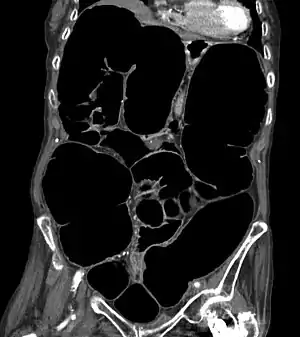

Pseudo-obstrução intestinal é uma síndrome clínica arrazoada como severo comprometimento na competência dos intestinos em fomentar alimentos para ulterior eliminação, através da defecação. É caracterizada por sinais e sintomas de obstrução intestinal, porém, à exegese examinatória, quaisquer lesões ao lúmen intestinal são nulas.[13] Manifestações clínicas podem concernir a dor abdominal, náuseas, distensão conspícua, vômitos, disfagia, obstipação intestinal e/ou diarreia, dependendo da porção do trato gastrointestinal engajada.[14] A condição pode incoar-se a qualquer idade, alternando dentre circunstâncias primárias (idiopática ou herdada), ou promovida por outra desordem (secundária).[15]